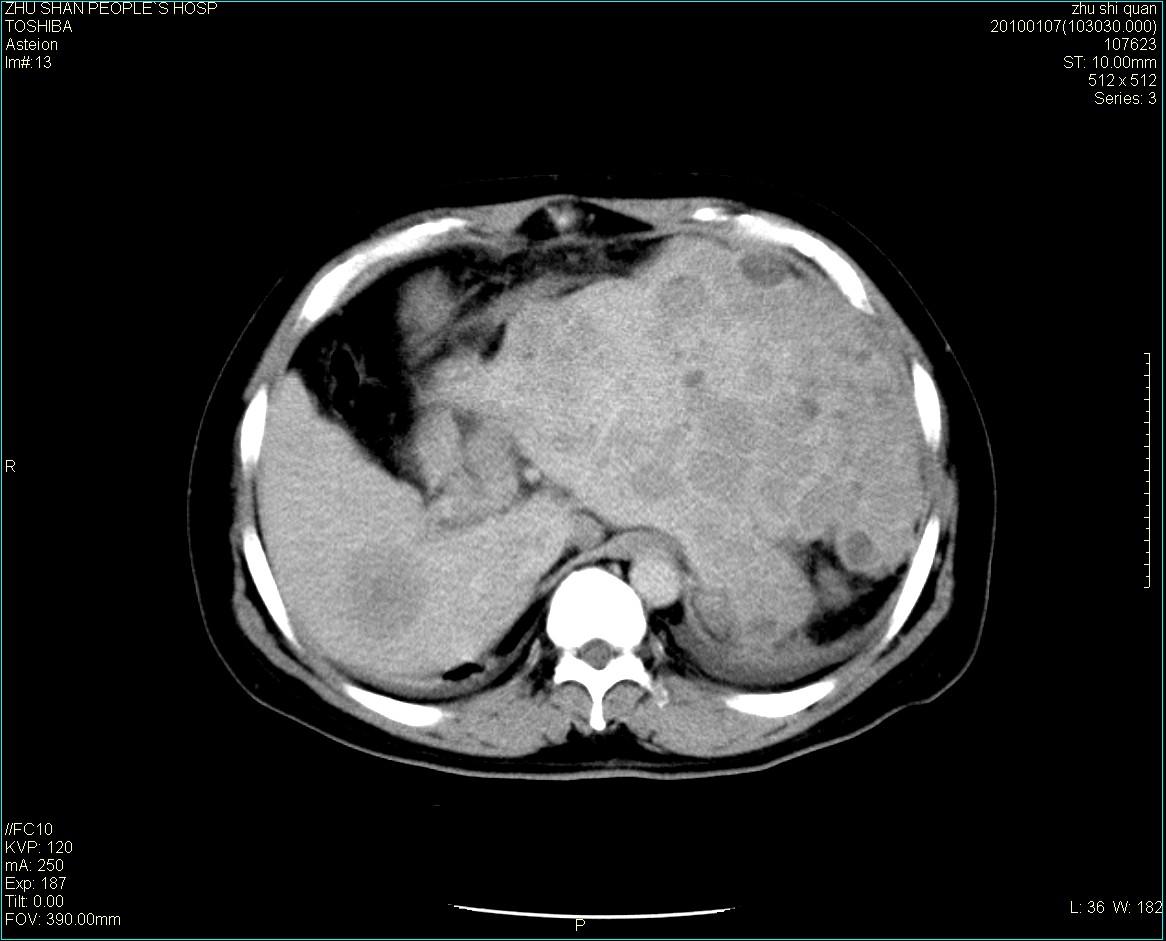

男性病人 肝ca两次术后,今日复查。

多发转移

肝、脾多发转移灶,胸腔积液

多发转移灶

1)肝癌并多发性转移。2)双侧胸腔积液(以左侧为甚)伴左下部分肺萎陷。

肝癌术后复发,考虑肝、脾多发转移。

肝癌术后复发,肝内、脾脏、腹膜后及腹膜多发转移,腹水,双侧胸腔积液(以左侧为甚)伴左下膨胀不全。

肝、脾多发转移灶,胸腔积液。

肝癌术后复发,肝内、脾脏、腹膜后及腹膜多发淋巴结转移,腹水,双侧胸腔积液。